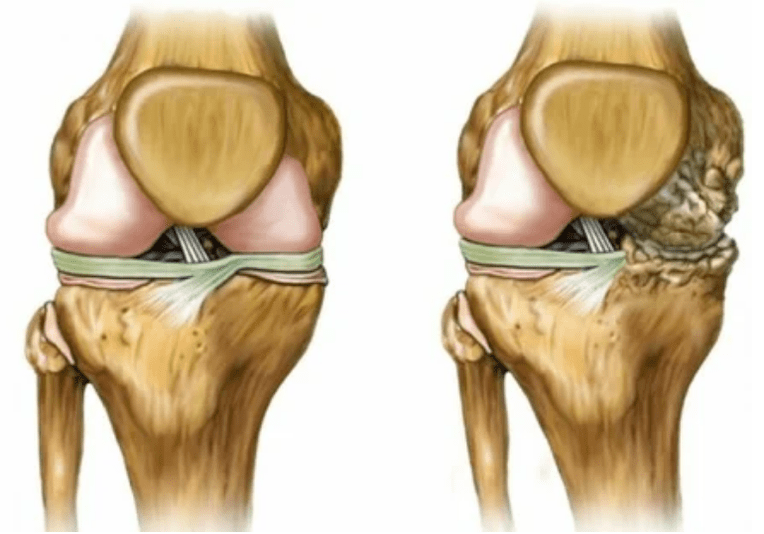

- Aşama 2. Arz eksikliği nedeniyle gerekli kartuşlar yok edilir, kıkırdağın yüzeyinde kemik büyümeleri oluşur. Ağrılar, daha belirgin bir karakter edinir, uzun bir dinlenmeden sonra yoğunlaşır, küçük fiziksel emek ile ortadan kaldırılır. Ağrıya iltihap eşlik eder. Kaslar gerilir, bu da zayıf veya ortalama bozulmuş motor fonksiyonlarına yol açar.

- 3 derece. Genellikle ağrılar vardır, eklemdeki değişiklikler nedeniyle uzuvları hareket ettirmek zordur. Lezyonlar geniş, çıplak görünüm için fark edilir hale gelir. Eklem bölgesinin deformasyonu meydana gelir, etkilenen alan şişer ve kırmızıya dönüşür. Ekstremite ekseni bozulur, bu da hareketin karmaşıklığına yol açar. Patolojik değişiklikler bağların kısaltılmasını kışkırtır. Subluishes ve kontraktürler ortaya çıkar. Bitişik kaslar kısaltılır veya gerilir, kasılma fonksiyonunun zayıfladığı.

uzuv deformasyonları. Hastalığın ihmal edilmiş bir formunda görünür, kıkırdak dokusunun tamamen yok edilmesini ve osteofitlerin görünüşünü gösterir. Bu durumda, eğrinin tüm uzuvları etkileyebileceği üst ve alttaki eklemler artar.